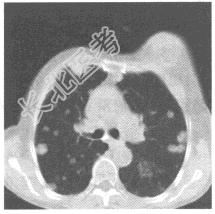

- 单项选择题女,67岁, 乳癌术后1年,胸部CT如图, 首先应考虑

E、肺转移瘤